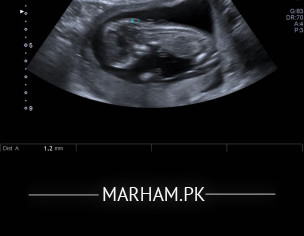

Plese tell me if you can guess the gender

Attach Photo here: